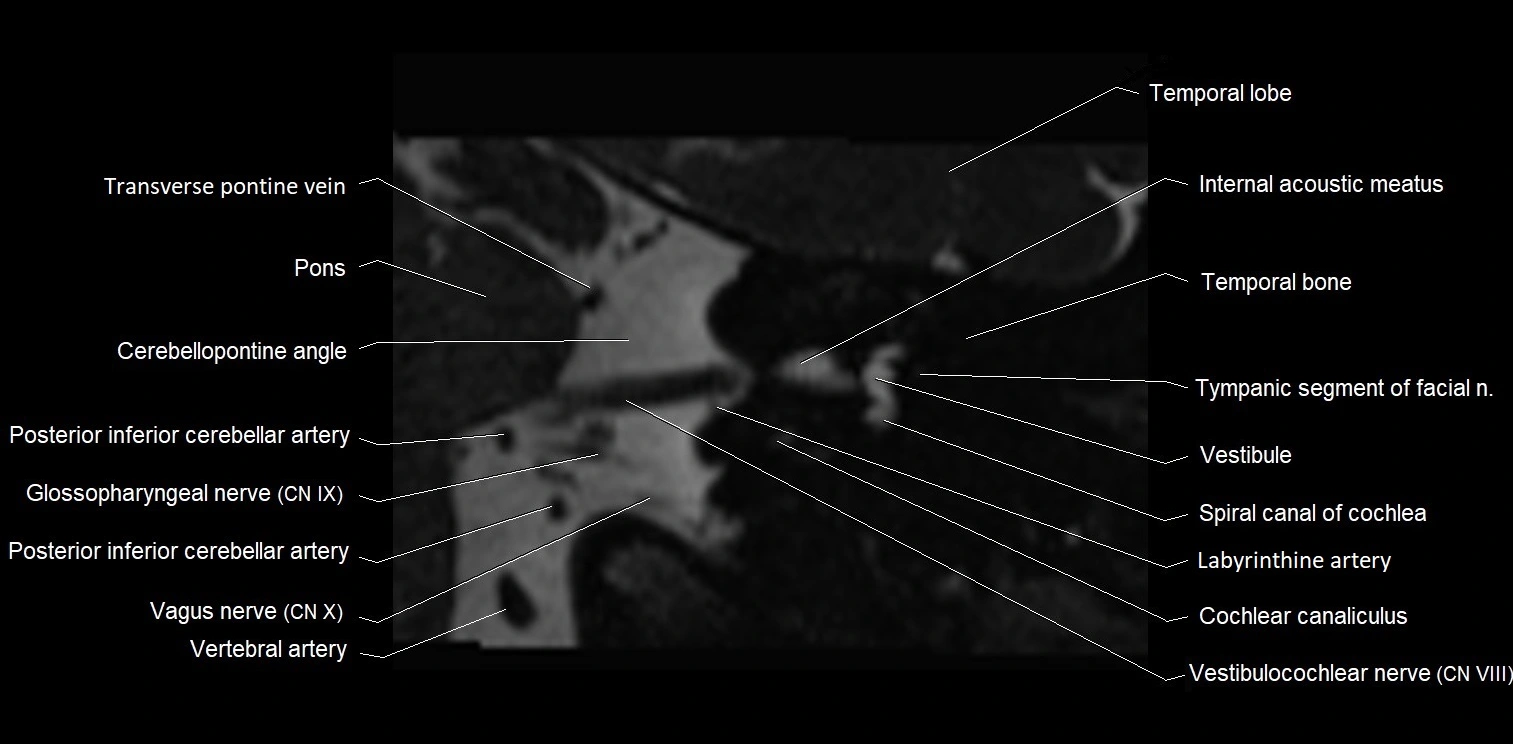

MRI images

image